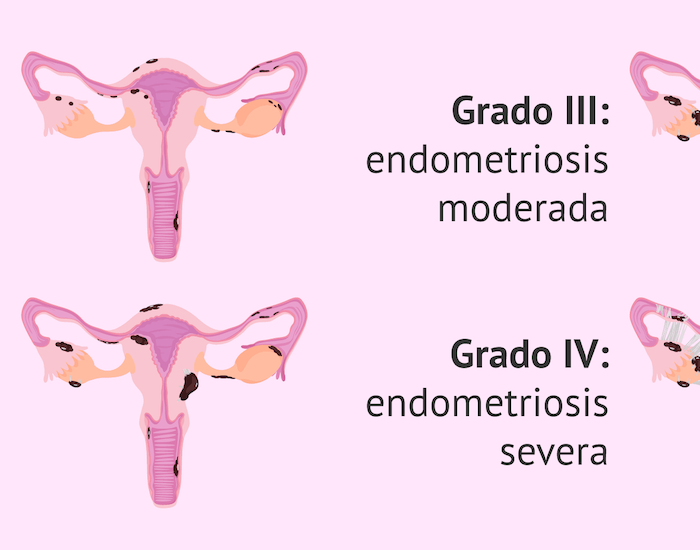

- Patologías ginecológicas frecuentes como quistes ováricos, endometriosis y miomas.

Un leve malestar es común, pero si el dolor es incapacitante, podría ser señal de endometriosis u otra afección que requiere atención médica.